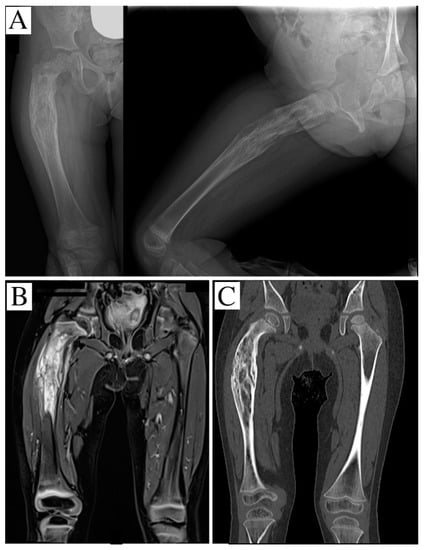

2. Case Report